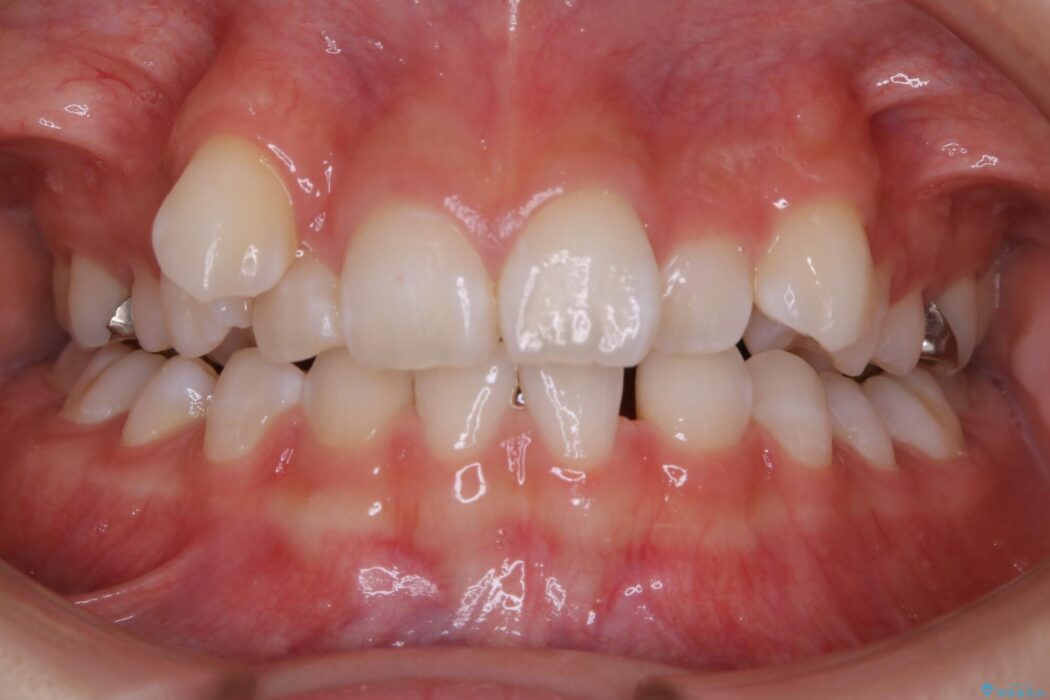

治療動機

飛び出た八重歯による歯列のガタガタを主訴に来院されました。

診査したところ叢生だけでなく生まれつき永久歯の欠損、いわゆる先天欠如により歯の本数が少ないため噛み合わせなどにも影響が出ている状態でした。

特殊な状況からの矯正治療となるため、抜歯する本数や位置、歯列を整えるにあたって必要なスペースの確保を慎重に計画し、インビザライン コンプリヘンシブパッケージでのマウスピース矯正を行いました。